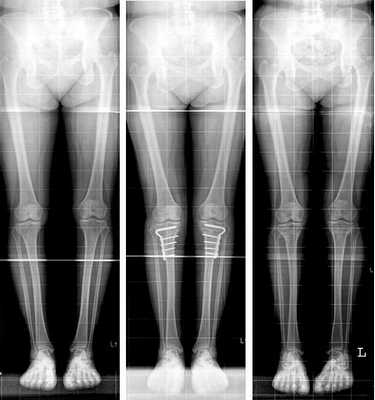

Часто встречающаяся ситуация - вальгусная деформация ног + наружная ротация + укорочение левого бедра 2 см. Слева деформация более выражена, поскольку деформированы были и бедро, и голень. Провели двухэтапную коррекцию. 1 этап - левое бедро, 2 этап - обе голени. Genu valgum (в отличие от genu varum) часто обусловлена деформацией бедренных костей. Поэтому для определения объема операции обязательно нужен рентген ног по всей длине.

При такой значительной деформации уже к 50 годам развивается деформирующий артроз коленных суставов преимущественно с вовлечением наружных отделов. Когда деформация прогрессирует, операция по исправлению оси становится уже не настолько эффективна. Кроме того, вальгусное колено намного сложнее в плане эндопротезирования.